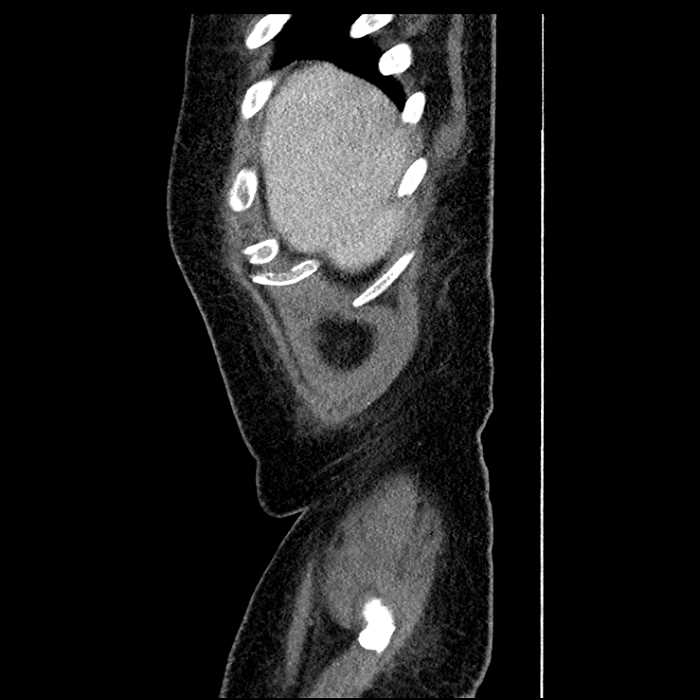

Age: 63

Sex: Male

Indication: Abdominal pain

• Large fluid density structure in hepatic segments 7 and 8 measuring 10 x 7 x 7 cm with internal septation and circumferential ill-defined low density compatible with edema

• Peripherally enhancing subcapsular collections along the anterior margin of the left hepatic lobe measuring 3 x 1 cm and 2 x 1 cm

• Clearly marginated fluid density structure in segment 7 and several other scattered tiny hypodensities, which likely represent cysts

Acute sigmoid diverticulitis complicated by a small contained perforation and a large abscess in the right hepatic lobe. Additional small subcapsular abscesses along the anterior margin of the left hepatic lobe.

• The classic CT imaging appearance is a double target sign with internal low density surrounded by an internal enhancing rim (capsule) and a low density external rim (edema)

Hepatic abscess showing the double target sign with low density internally surrounded by a thin inner enhancing rim (red arrow) and ill-defined outer low density rim (yellow arrow). Blue arrow indicates an internal septation. Red arrows: additional smaller subcapsular abscesses. Red arrow: focal contained perforation associated with diverticulitis.